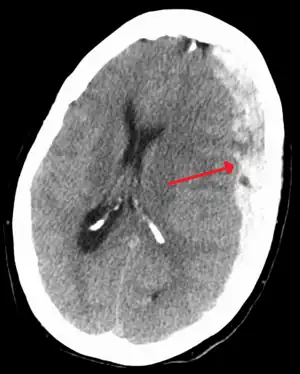

Acute-on-chronic subdural hematoma

Acute traumatic subdural hematoma

Acute on chronic subdural hematoma

A subdural hematoma demonstrated by CT